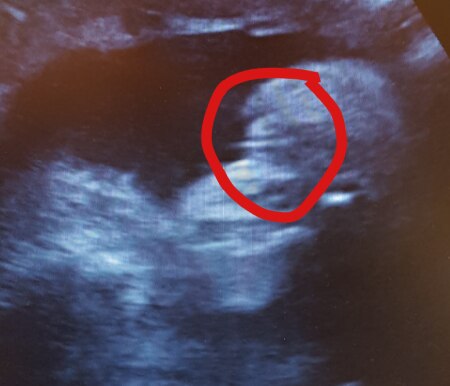

Hallo ihr In der 25+4 ssw hatte ich noch mal das outing, das diesmal auch in den mutterpass eingetragen wurde. Was sagt ihr? *.* Rosa shoppen kann beginnen, oder?

Bild zu Outing 25+4 ssw - Schwanger - wer noch? Rund um die Schwangerschaft